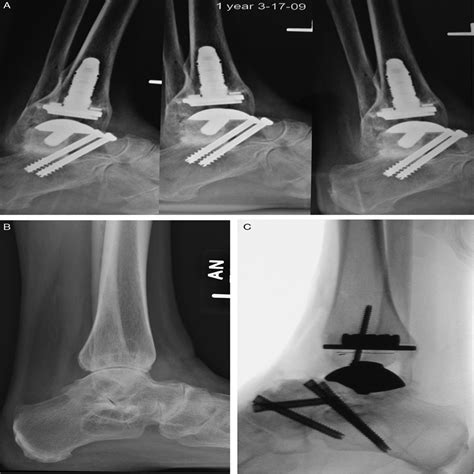

• Fixation: The bones are aligned and held in place using screws, plates, or rods. These fixation devices provide stability while the bones heal and fuse together.